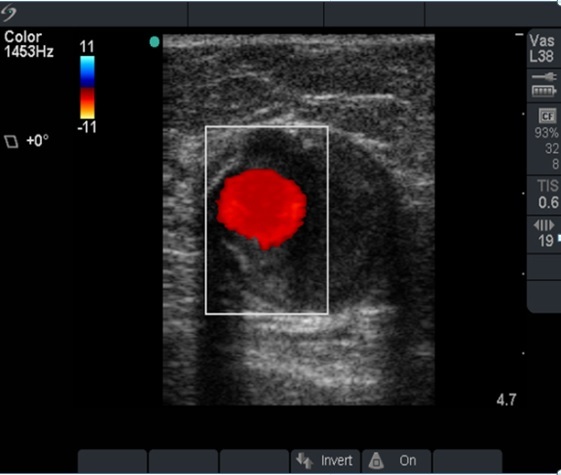

PIV Thrombus with Color Image